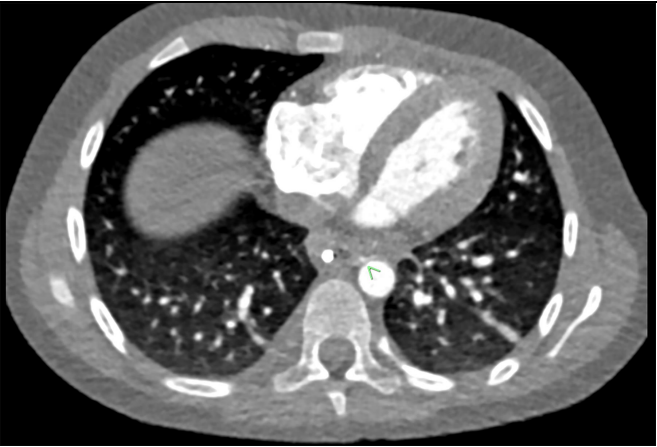

We report the case of a previously healthy 8-year-old female patient weighing 26.4 kilograms. She presented to her local pediatric hospital emergency department with abdominal pain 14 hours after swallowing a 20 mm 1.5V Lithium button battery (BB) while jumping on a trampoline with the battery in her mouth. An abdominal radiograph was performed demonstrating the position of a circular radio-opaque foreign body in the distal esophagus, initially thought to be a coin. Repeat imaging the object was noted to have smooth edges with concern to be a button battery and the patient was transferred to a hospital with esophagoscopy capabilities. Twenty hours after ingestion she underwent removal of the BB with esophageal endoscopy under general anesthesia (GA). At this procedure a circumferential erosion in the lower ¼ of the esophagus was identified. She was transferred to the pediatric intensive care unit of our tertiary care center 24 hours after removal, prior to which she had one episode of blood-tinged emesis.  She underwent repeat endoscopy under GA to define the extent of the injury and a black eschar was documented involving 50% of the distal anterior esophagus. (Figure 1) Twenty-four hours later she underwent a third GA for thoracic Magnetic Resonance Angiography (MRA) and a Computed Tomography Angiography scan to further evaluate for any extension of the esophageal erosion to surrounding critical structures.

Figure 1: Esophagoscopy showing eschar and erosion in the distal anterior esophagus.

Figure 1